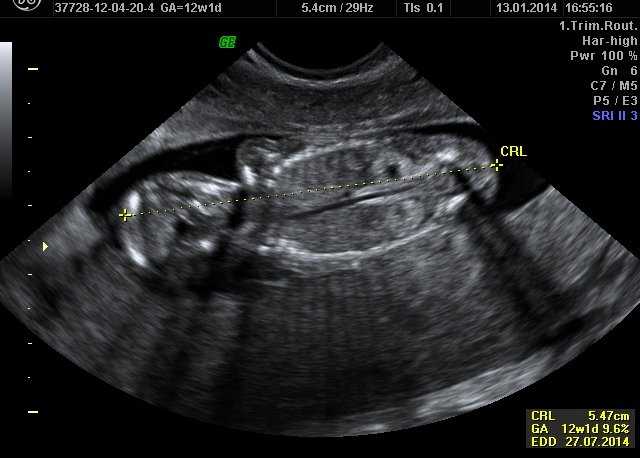

İkili test, gebeliğin erken döneminde yapılan, anne kanındaki belirli hormon değerlerini ve ultrason ölçümlerini birleştirerek Down sendromu gibi kromozom anomalilerini risk analizine tabi tutan bir tarama testidir. Bu test, genellikle 11–14. haftalar arasında uygulanır ve sonuçlar, olası riskin düşük mü yüksek mi olduğunu gösterir.

- Ultrason Ölçümü: Bebeğin ense kalınlığı (NT) ölçülür.

İkili test kaçıncı haftada yapılır sorusunun cevabı önemlidir. Testin doğruluk oranı 11–14. gebelik haftaları arasında en yüksektir. Bu dönemde yapılan ölçümler, hem hormon değerlerinin hem de ultrason bulgularının güvenilirliğini sağlar.